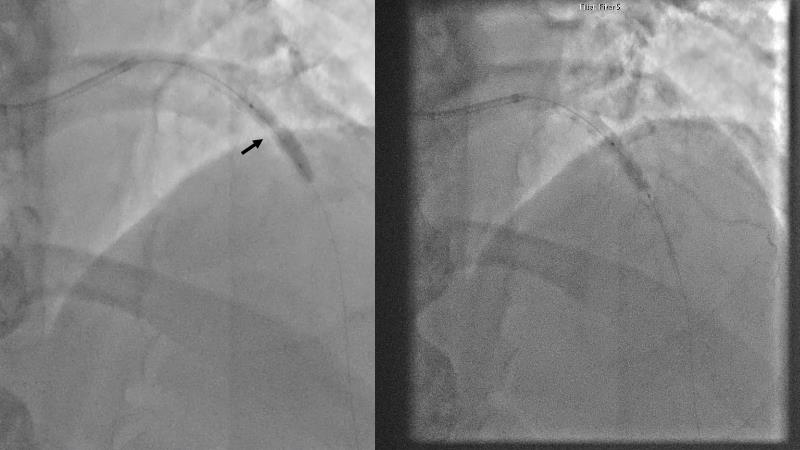

Watch this session to gain case-based insights on using DCBs in complex settings. Learn valuable tips and tricks for optimal DCB application, including the best timing and situations for their use. Discover how to effectively implement a hybrid strategy that combines DES and DCB when needed.

- To get a case based experience on how to use a DCB in complex settings

- To learn about tips and tricks on how and when to use a DCB: the ideal time and situation of DCB application in various complexities